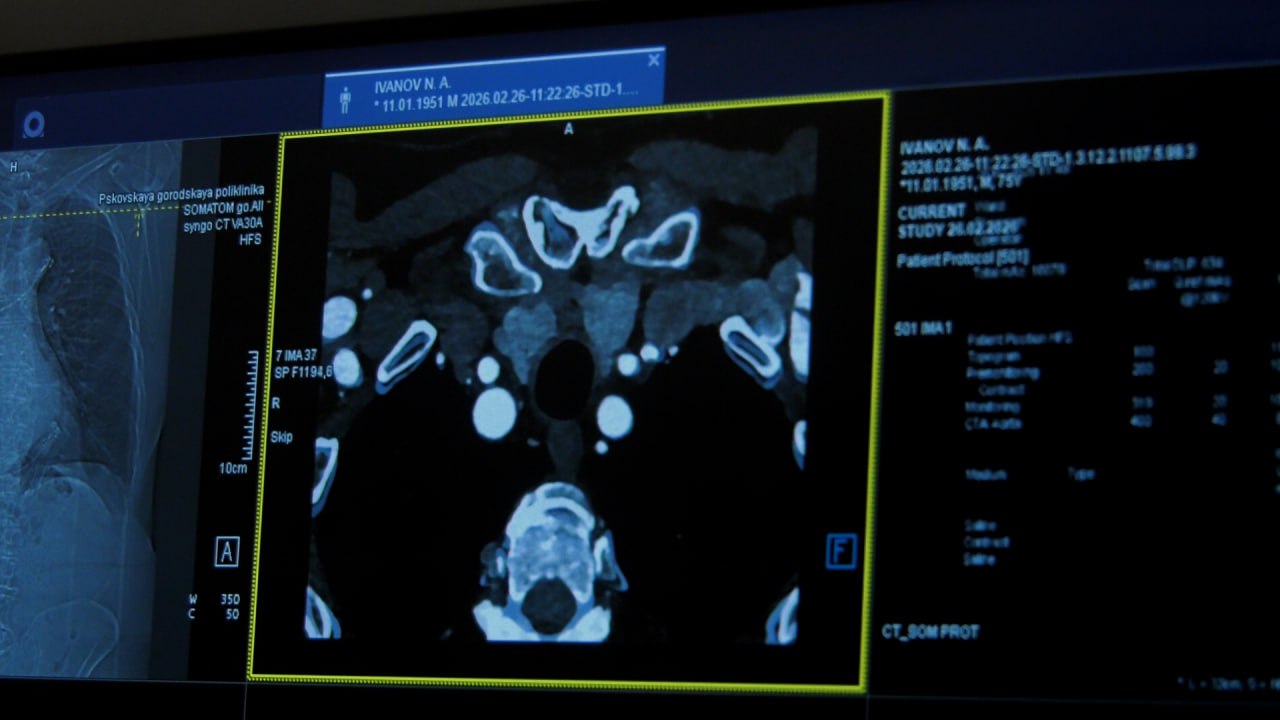

Современная диагностика без очередей и с максимальной точностью. В поликлиниках Псковской области новое оборудование помогает врачам выявлять болезни на ранних стадиях. Как цифровые технологии меняют качество медицины?